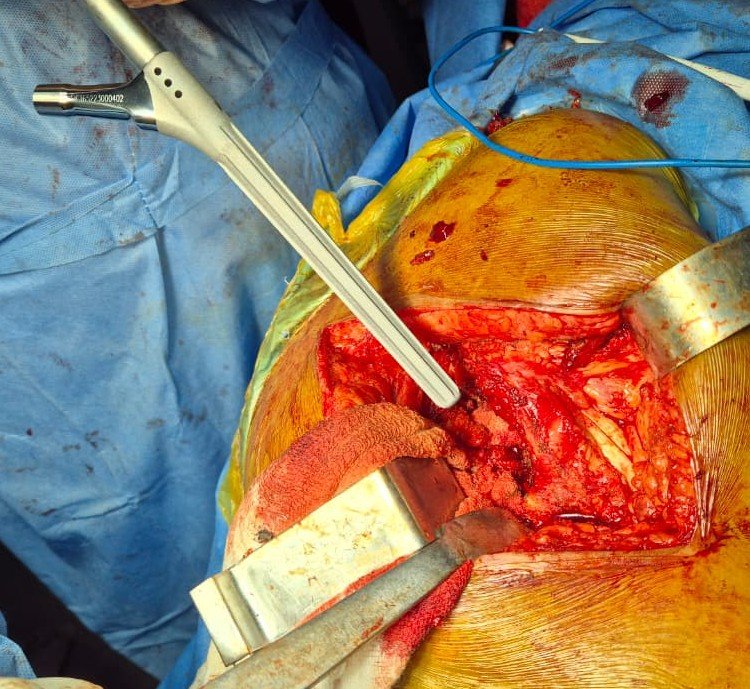

Canal Reaming

Stem Placement

Femoral Stem with Metal Head

Trial Reduction with Stability Evaluation